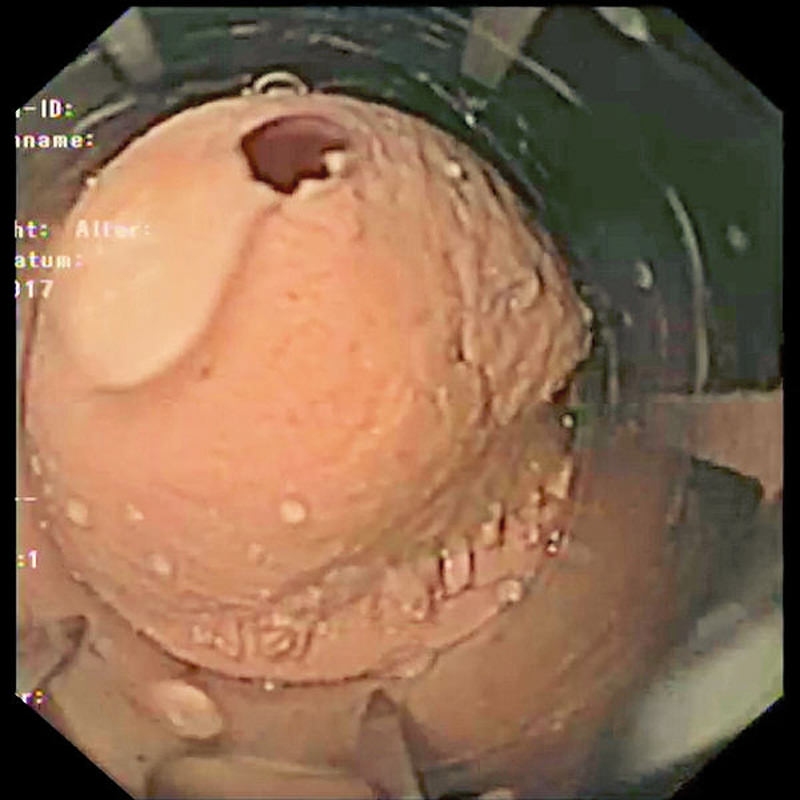

Simulator Gastro združuje možnosti realističnega anatomskega modela in usposabljanja za intervencijsko endoskopijo. Veliko število različnih vložkov omogoča zdravljenje polipov, kot so vbrizgavanje, dvigovanje, rezanje in odstranjevanje, simulacija zaustavitve krvavitve, stentiranje in drugo. Simulator in vložki so izdelani iz popolnoma umetnega materiala.

- Varikacijska ligatura

- Vstavljanje stentov v požiralnik, želodec in dvanajstnik

- Izbirna razširitev: Modul EUS - usposabljanje za endoskopski ultrazvok (EUS) z možnostjo punkcije (FNA)